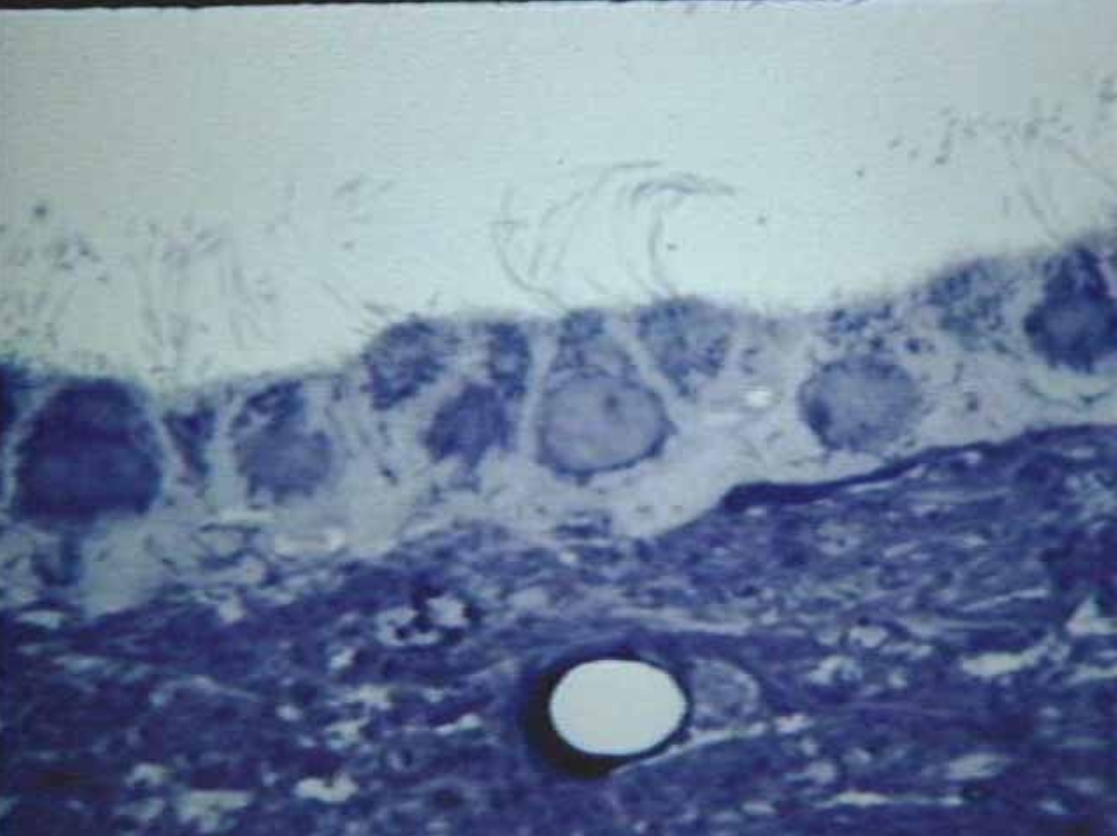

What is this?

Ependymal Cells (Microscopic real view)